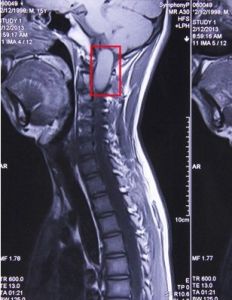

對啞鈴形腫瘤,多數可一期切除,但對某些巨大型者,也可二期切除。但無論是一期或二期手術,均應先切除管內部分,否則有可能間接損傷脊髓。對長入胸腔或腹膜後的啞鈴形腫瘤,有時可能需要開胸或經腹膜後手術。 馬尾部的神經鞘瘤,如體積較大,與神經粘連緊密或將其包裹,則手術難度大,易造成馬尾神經損傷。應利用顯微技術,先行囊內切除或分塊切除,然後仔細分離神經。近年來,由於醫療設備的進步,CT和MRI的普及、顯微技術的套用,診斷水平大大提高,手術全切率或成功率明顯上升。